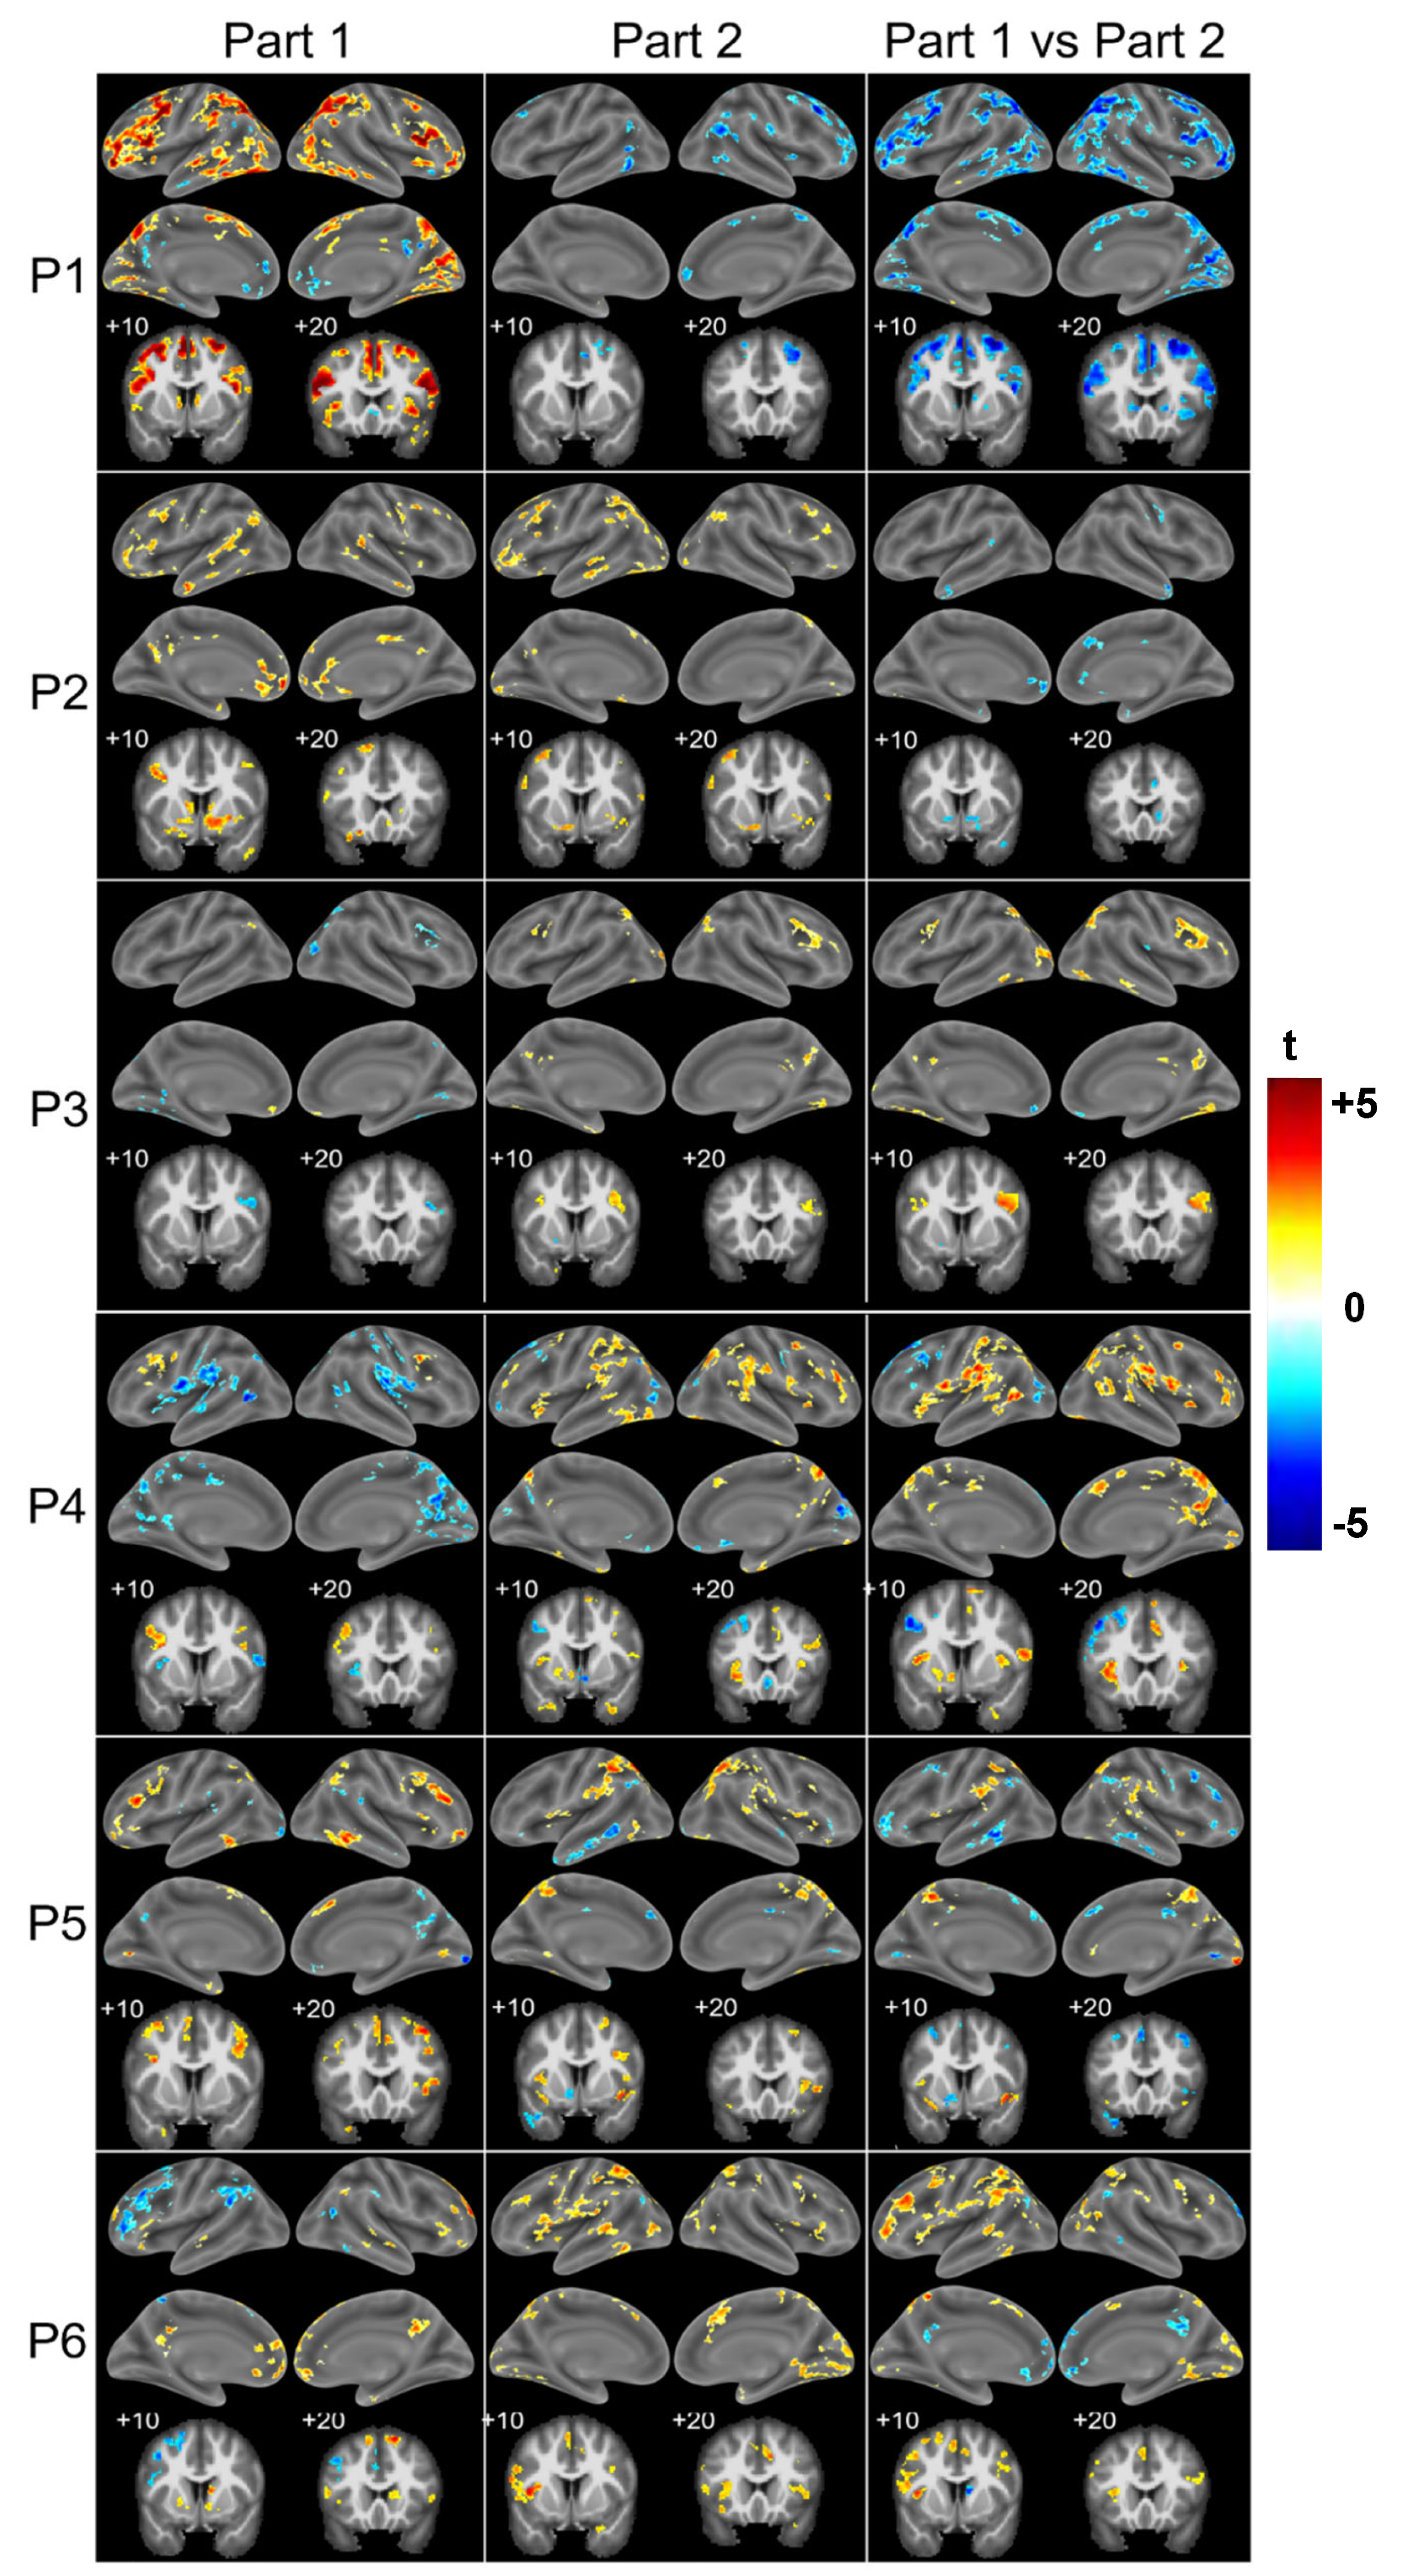

3.2. Patient Population

4.2. Two Profiles of Network Resilience After Severe COVID-19